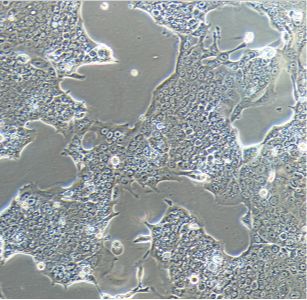

人皮肤黑色素瘤细胞SKMEL5(STR) 新品

SK-MEL-5是从皮肤组织中分离的黑色素瘤细胞系,所述皮肤组织得自24岁的白人女性恶性黑色素瘤患者。该细胞系是一种合适的转染宿主,也可作为在患有黑素瘤的患者中检测黑素瘤特异性抗体的靶细胞来源。这是T. Takahashi及其同事分离出的一系列非常广泛的黑色素瘤细胞系之一。在裸鼠中;形成恶性黑色素瘤